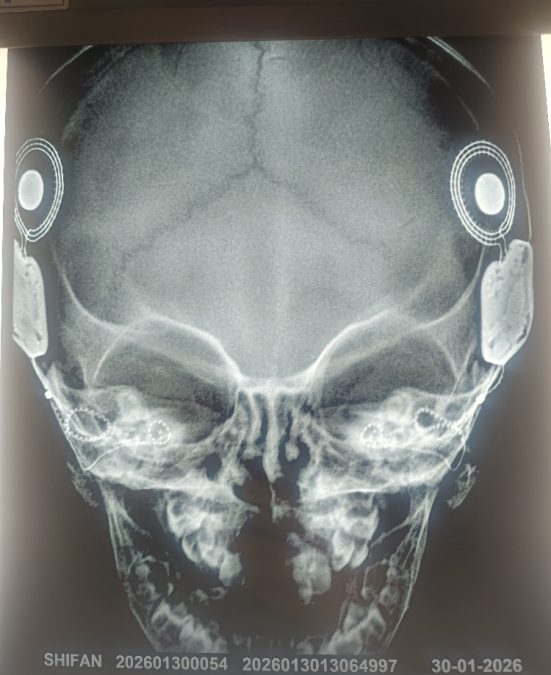

Dr Mohnish Grover, who has done the highest number of Cochlear implants, could not find a better occasion than National Training Programme on Cochlear Implant to perform an implant using Active Insertion Monitoring (AIM) Technology for the first time in the world to a kid suffering from Auditory Neuropathy Spectrum Disorder – a rare condition where the inner ear detects sound normally but the auditory nerve fails to transmit it to brain.

Dr Mohnish Grover, who is the youngest president of All India Rhinology Society, said that the AIM technology ensures an extremely slow, controlled, and atraumatic electrode insertion, minimising inner ear trauma.

“Normally, electrode insertion during cochlear implant surgery takes approximately 30–60 seconds as against AIM-guided insertion, which takes 410 seconds, ensuring maximum protection of delicate cochlear structures,” he said.

Grover said that AIM technology is superior as the intraoperative cochlear responses are exceptionally strong, reaching levels of 100–170 as against typical responses which are in the range of 30–60.